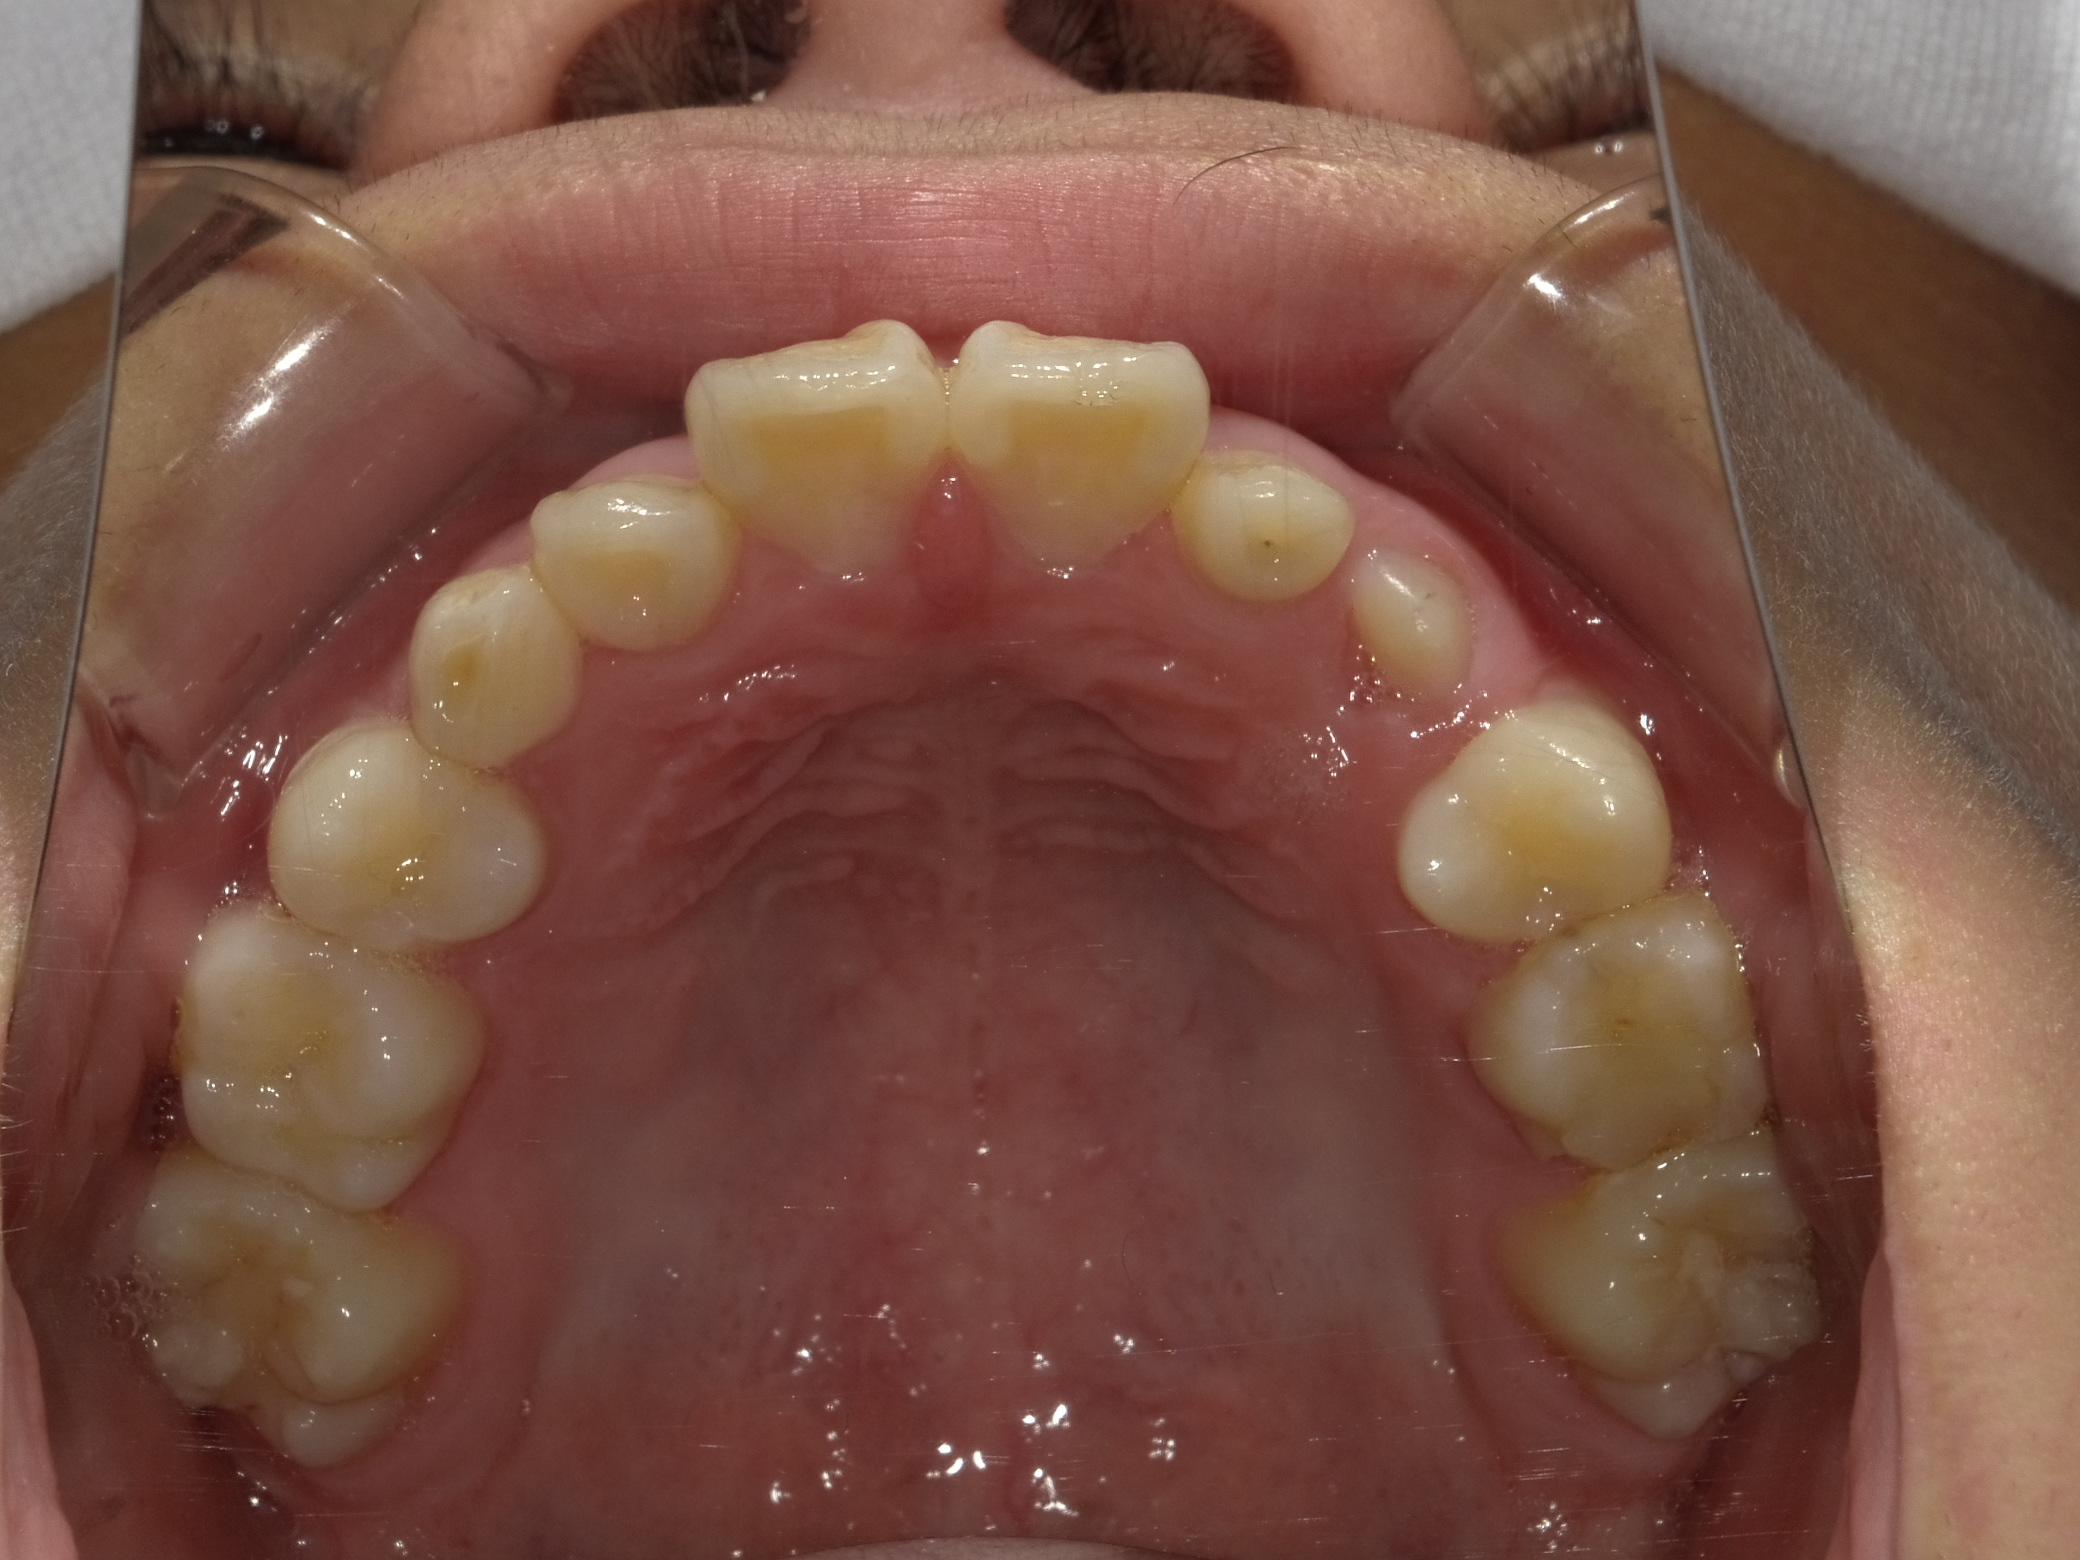

9歳男性 スペース不足(永久歯が並ぶ場所がない)・交叉咬合(一部分だけかみ合わせが反対)

治療内容:インビザライン・ファースト